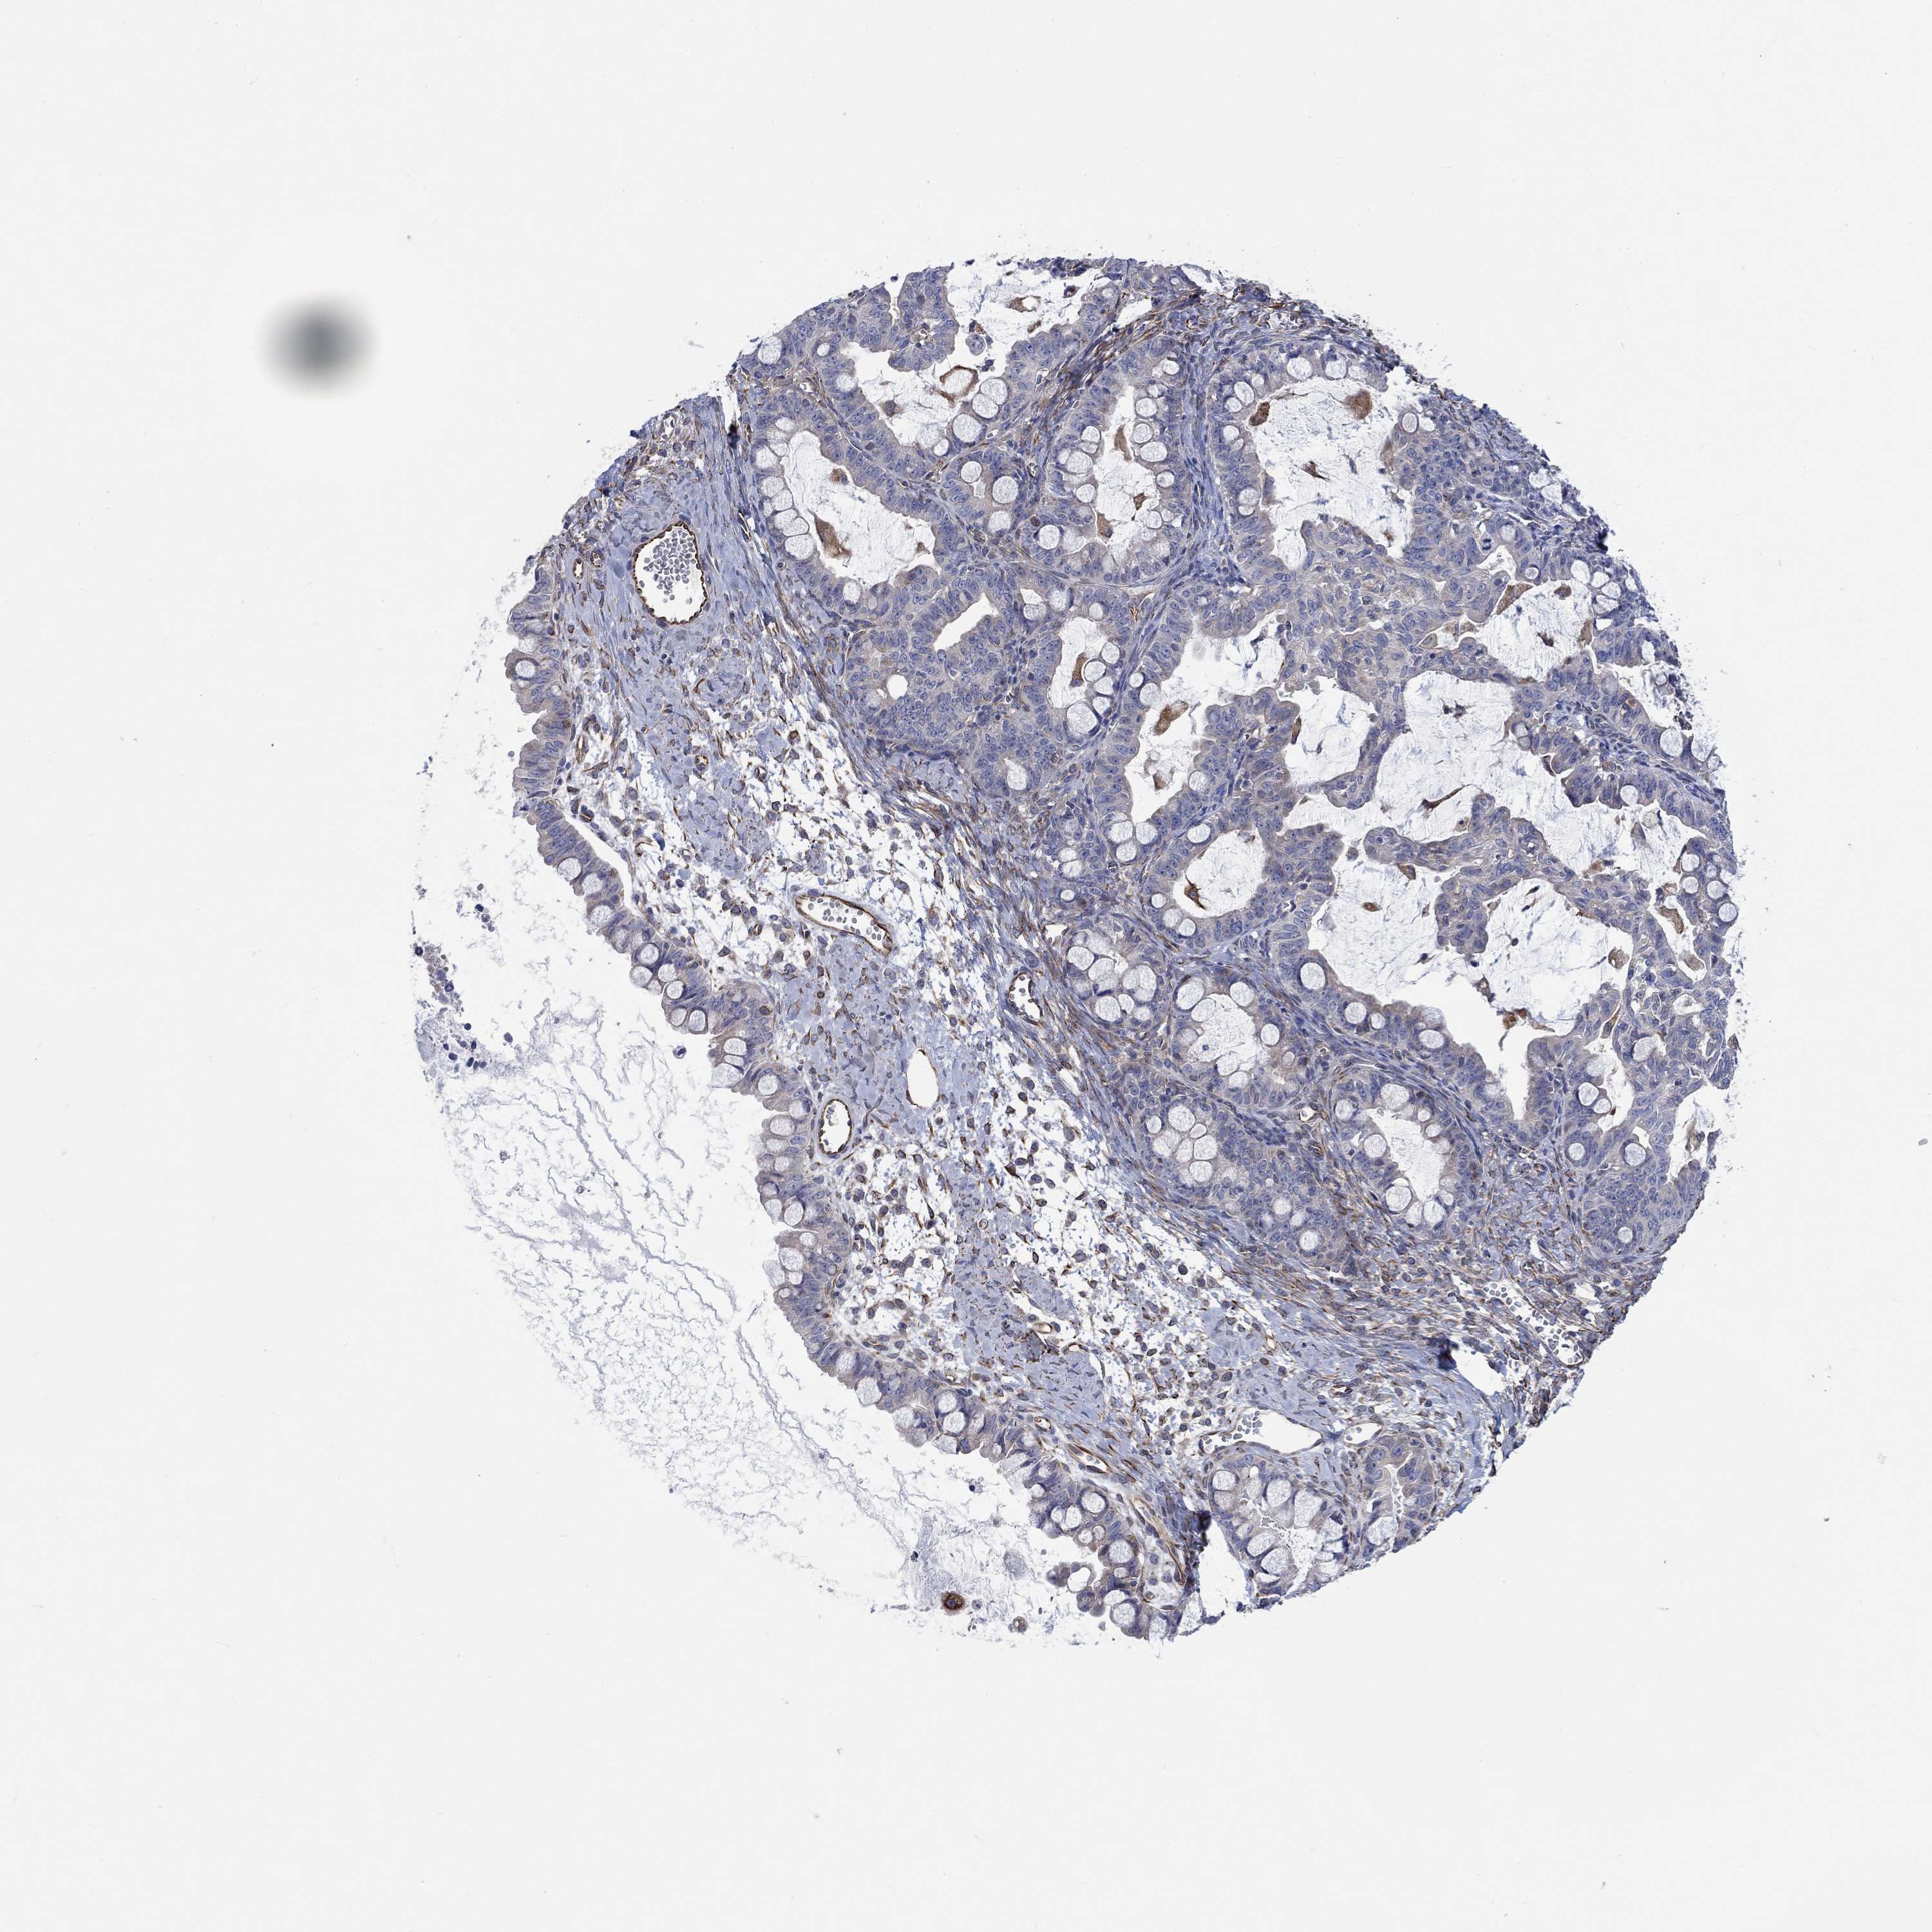

OVARIAN CANCER - Protein expressioni

A mouse-over function shows sample information and annotation data. Click on an image to view it in a full screen mode. Samples can be filtered based on level of antibody staining by selecting one or several of the following categories: high, medium, low and not detected. The assay and annotation is described here.

Note that samples used for immunohistochemistry by the Human Protein Atlas do not correspond to samples in the TCGA dataset.

Antibody stainingi

Antibody staining in the annotated cell types in the current human tissue is reported as not detected, low, medium, or high, based on conventional immunohistochemistry profiling in selected tissues. This score is based on the combination of the staining intensity and fraction of stained cells.

Each image is clickable and will lead to virtual microscopy that enables deeper exploration of all samples and also displays staining intensity scores, fraction scores and subcellular localization as well as patient and tissue information for each sample.

Antibody HPA007266

Staining

High

Medium

Low

Not detected

Intensity

Strong

Moderate

Weak

Negative

Quantity

>75%

75%-25%

<25%

None

Location

Nuclear

Cytoplasmic/membranous

Cytoplasmic/membranous,nuclear

Cystadenocarcinoma, serous, NOS

Cystadenocarcinoma, mucinous, NOS

Carcinoma, endometroid